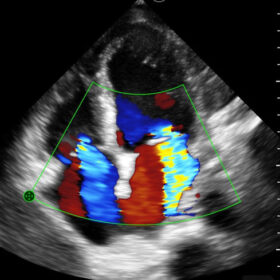

Mindray I3P WiFi Probe Image Gallery and Videos

Display mode: B, B/M, and Color, PW, PDI